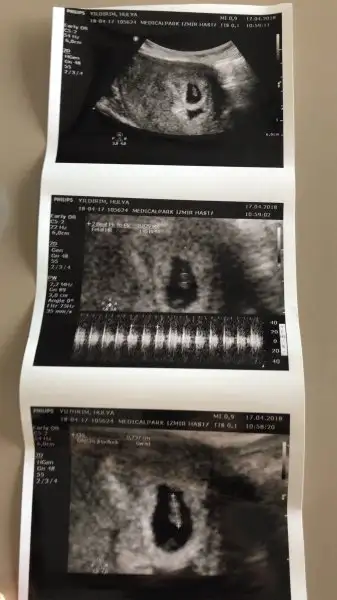

Kızlar 6+1 haftalık görüntü karından. Bana da tahminde bulunur musunuz

• 57C845F6-3875-4AD1-9908-8A555A704A12.webp

18,3 KB · Görüntüleme: 285

Çok erken ama merak ediyorum sağda gibi değil mi plesentası ilerki haftalarda tekrar danışırım insallah